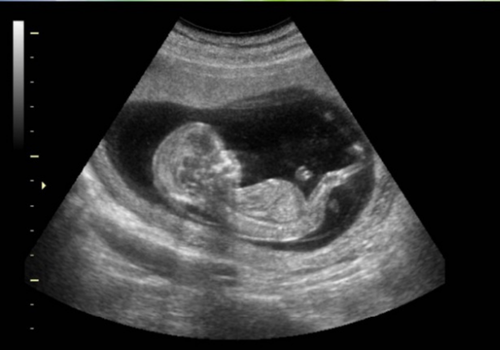

La ecografía es mucho mejor que todos los demás métodos para calcular la edad gestacional, por lo que se recomienda hacerla siempre dentro del primer trimestre, para ver el embrión y medir el saco gestacional, que son los elementos en los que se basa el diagnóstico de normalidad. A los 20 mm, en promedio, ya debe existir un embrión visible.

La ecografía es un elemento fundamental para diagnosticar las alteraciones de los anexos ovulares, aunque la clínica orienta hacia lo se debe pesquisar. Generalmente, la ecografía señala dónde está ubicada la placenta y las zonas de desprendimiento que originan la hemorragia o las contracciones, lo que permite adoptar conductas con respecto a la actividad física posterior de esa paciente.

Además, la ecografía permite pesquisar anomalías estructurales de la placenta como, por ejemplo, cotiledones aberrantes o zonas membranosas con vasos sanguíneos y alto riesgo de hemorragia, lo que se ve en el doppler. Este último también permite detectar la presencia de vasa previa, vasos sanguíneos cercanos a las membranas del polo inferior, que condicionan un mayor riesgo de sangrado.